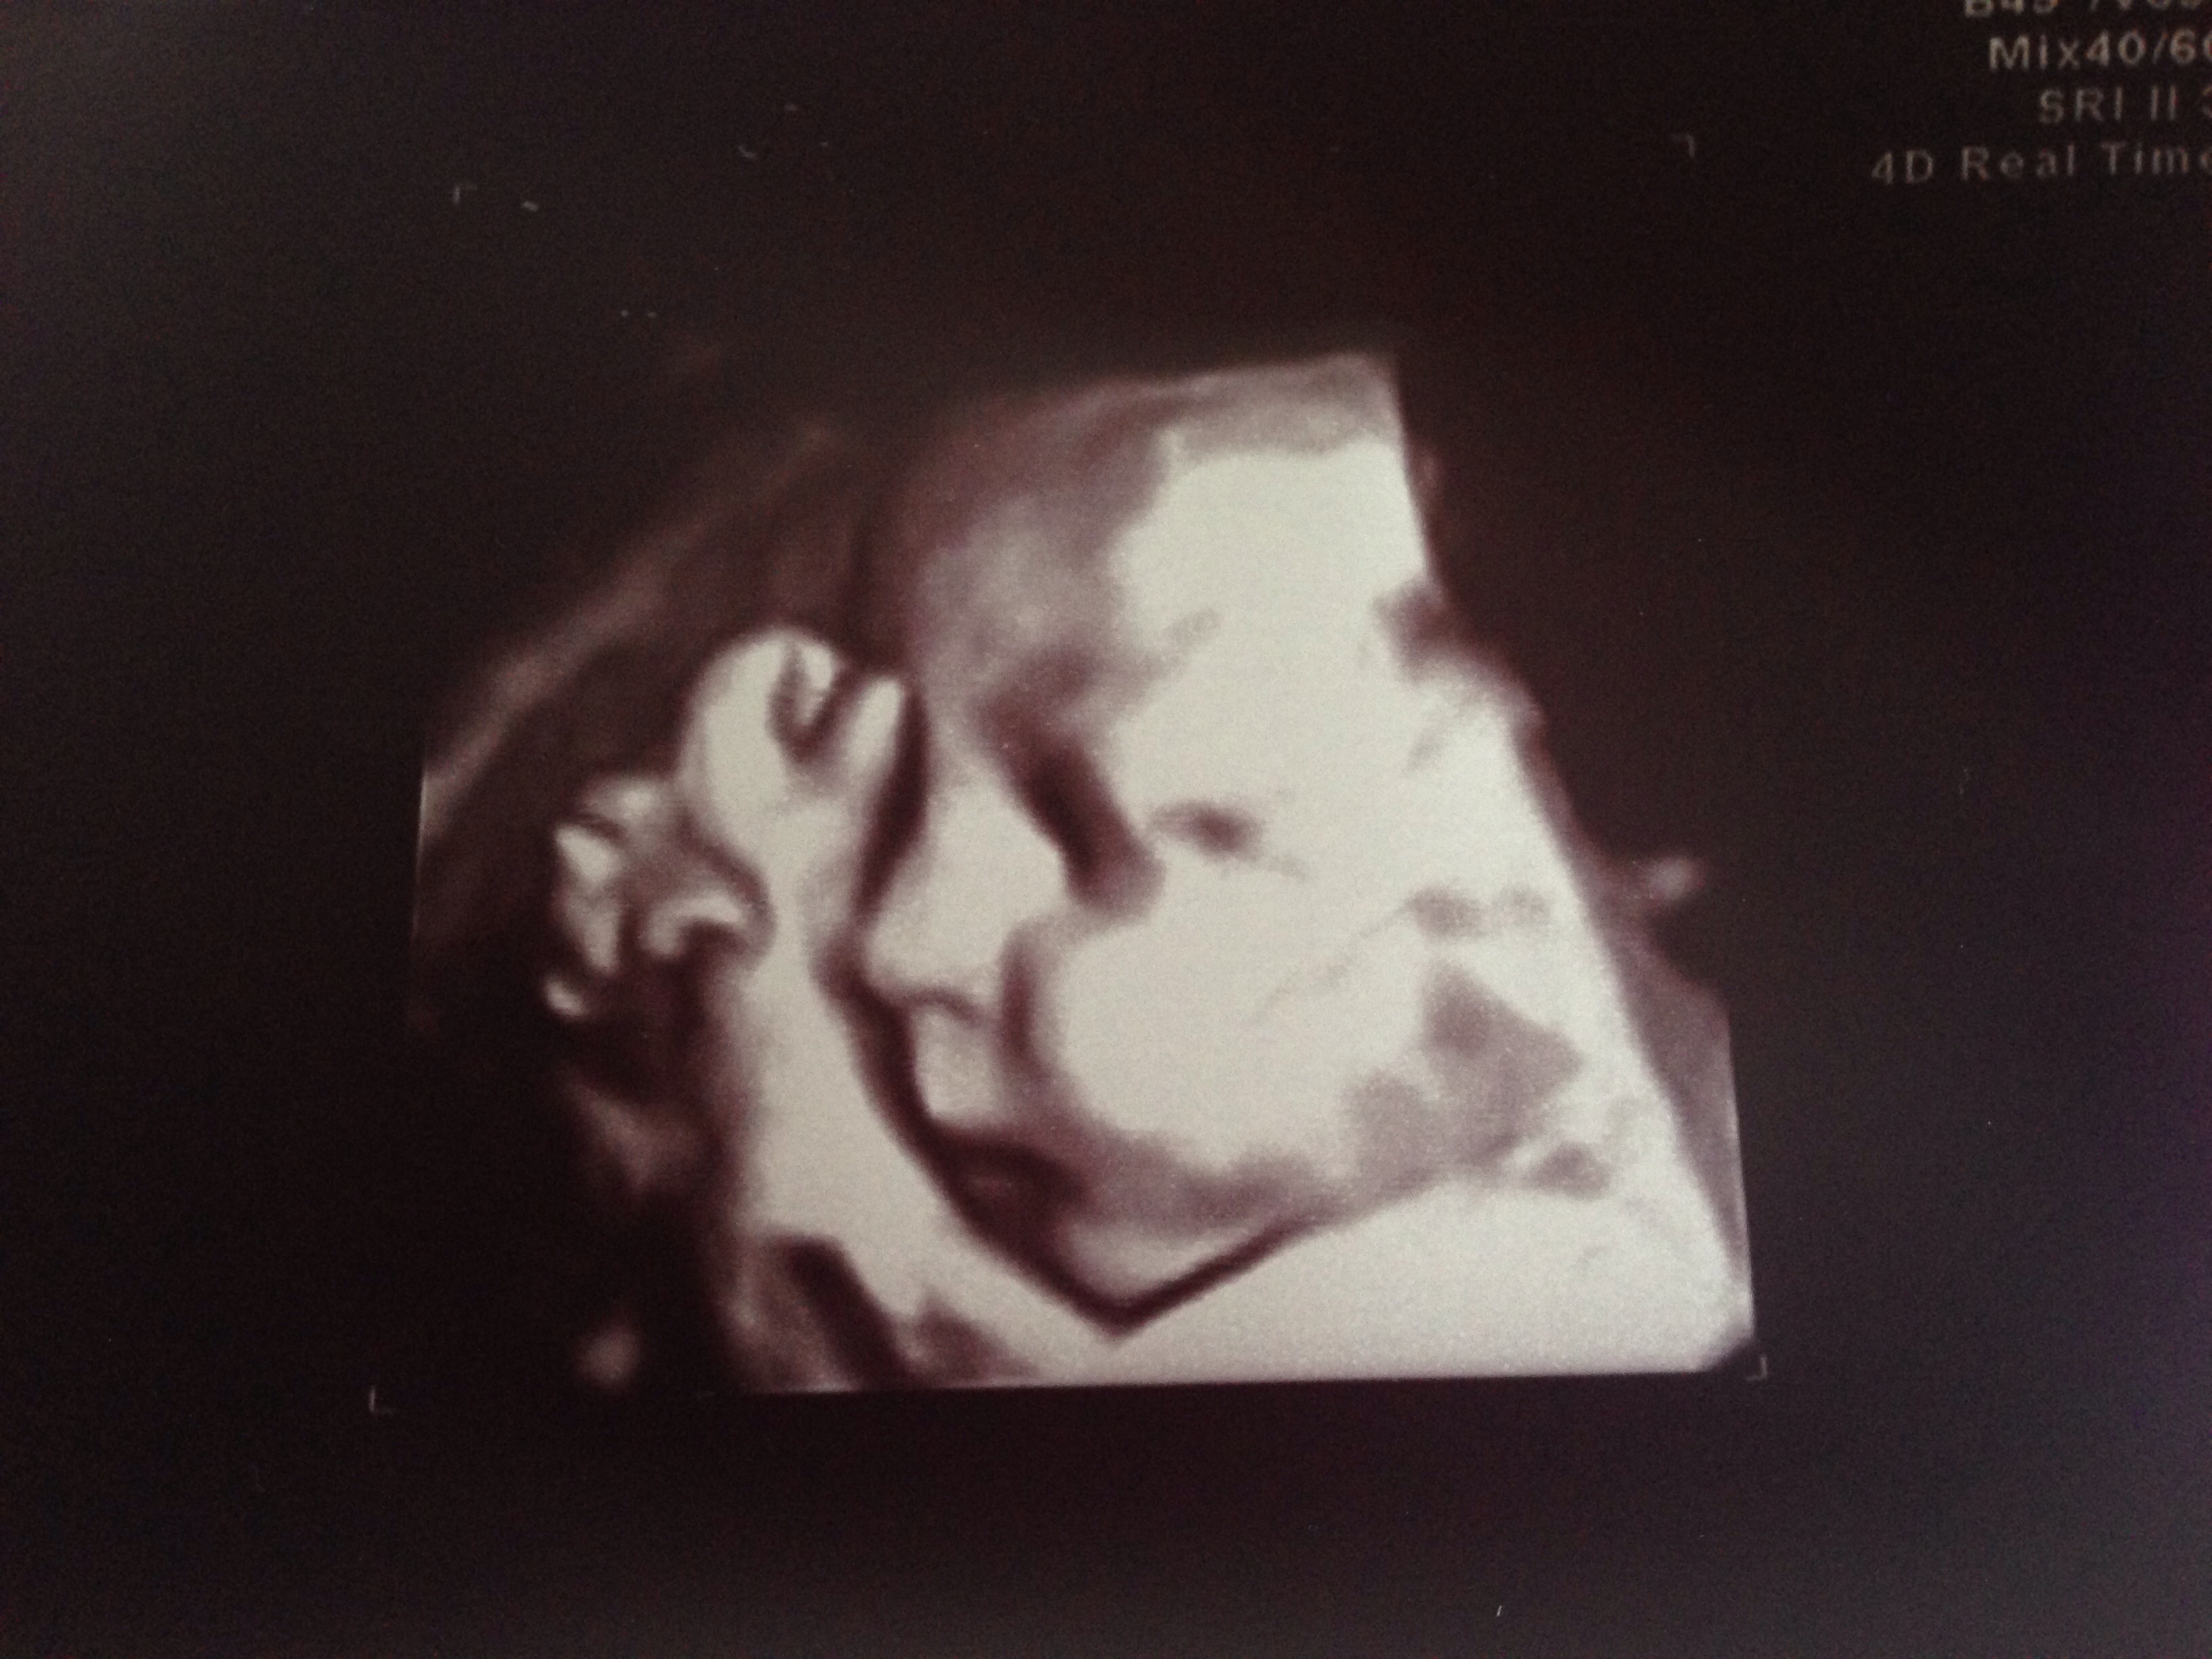

Mornin sonogram at 32w2d... Cutest baby face ever!! Weighing in at 4lb6oz scares me silly!! Praying I don't have a giant baby but they claim that's 50th percentile! Sono tech also confirmed my suspicions!! Lots of hair on her head explains all my crazy heartburn!

@Gbseder I usually think the 3D pics are super creepy, but your baby is adorable already!!

Thanks @liberty95!! My family hasn't responded so well to the ones so far either- same reaction to their super creepiness but this one finally really captured her cuteness!! Xoxox